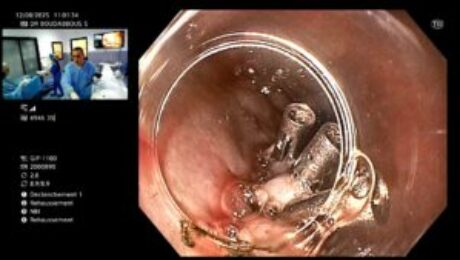

Traitement de l’achalasie de l’oesophage par POEM

samedi, 16 août 2025

par Sami Boudabbous

Voici une description claire de l’achalasie et de son traitement par POEM (Peroral Endoscopic Myotomy) : 🧠 Qu’est-ce que l’achalasie ? L’achalasie est une maladie rare de l’œsophage caractérisée par : Une absence de relaxation du sphincter inférieur de l’œsophage (SIO). Une perte de la motricité normale de l’œsophage. Cela entraîne des difficultés à avaler